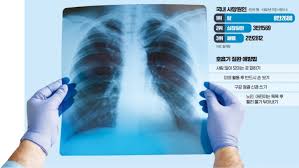

폐렴 연관 패혈증

겨울철 가장 흔한 감염 질환 중 하나가 바로 폐렴입니다. 특히 독감(인플루엔자)에 걸린 후 폐렴으로 발전하는 경우가 많고, 면역력이 약한 사람들은 세균성 폐렴이 패혈증으로 진행될 위험이 큽니다.

• 원인: 폐렴구균, 황색포도상구균, 인플루엔자 바이러스 감염 후 2차 세균 감염

• 증상: 고열, 오한, 호흡 곤란, 기침, 가래, 가슴 통증, 의식 저하

• 예방법: - 독감 예방접종 및 폐렴구균 예방접종 필수 (특히 65세 이상, 만성질환자)

- 감기 증상이 심해지고 고열이 지속되면 즉시 병원 방문